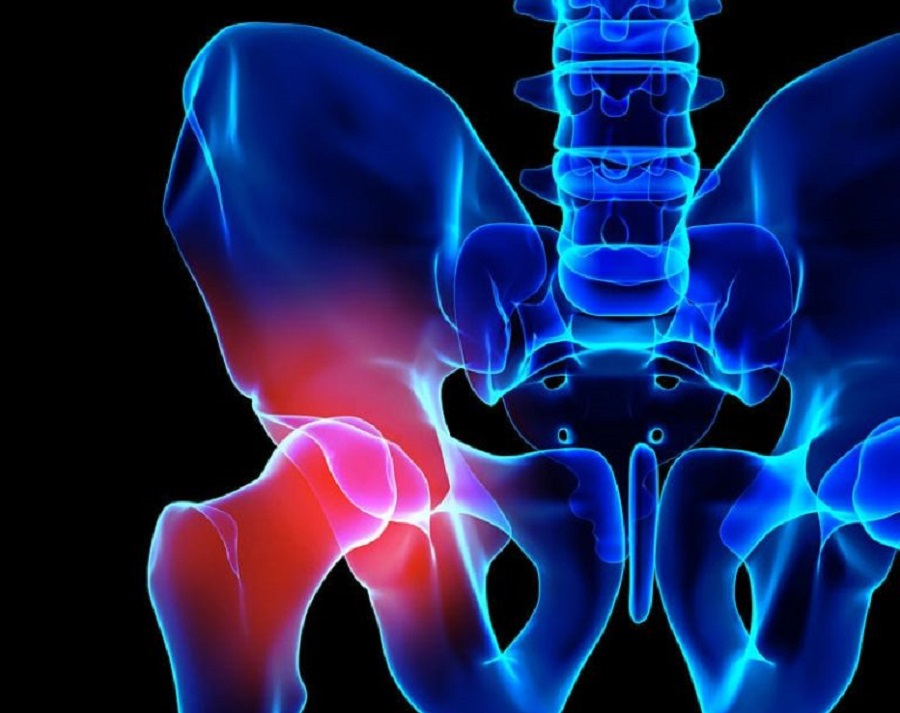

Ciudad de México.- La coxartrosis es la artrosis localizada en la zona de la cadera, la cual se produce por un desgaste del cartílago de la cadera. Es habitual en los adultos mayores y es una de las principales causas de roturas y fracturas de cadera. Su tratamiento se basa en antiinflamatorios acompañados de fisioterapia y rehabilitación, pero en casos muy avanzados en los que el hueso y el cartílago sufren un gran desgaste es requerida una intervención quirúrgica para colocar una prótesis de cadera y con ello ayudar a mejorar la calidad de vida del paciente.

“Ella sufría coxartrosis bilateral, degeneración de ambas caderas, ya no hay movilidad, hay dolor y el cartílago cuesta mucho trabajo que Dios lo regenere, pero si Dios no le hubiera regenerado ya su cartílago ella ahorita necesitaría prótesis en la cadera”, explicó el doctor González López.